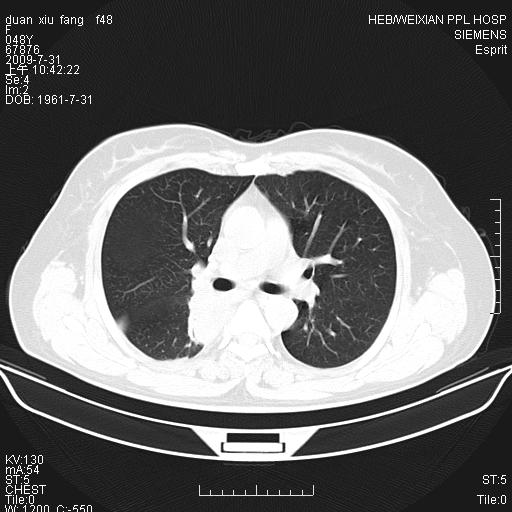

标题: CT22224:肺部肿块

f,48,主因咳嗽咳血来我院检查,无发热。

1)右肺下叶背段团块状软组织密度影;建议抗炎治疗后复查排除肿瘤性病变。2)右侧少量胸腔积液。

谈一谈个人的看法:机器性能应该不错,可惜扫描方法不太正确,即没有及时薄层扫描图像,也没有增强检查,这样的检查方法不正确的图片拿来研究只能是猜一猜:右肺下叶阻塞性改变,建议进一步检查删除肺癌。

支气管镜检查未见异性细胞,抗炎治疗20天,肿块明显缩小。